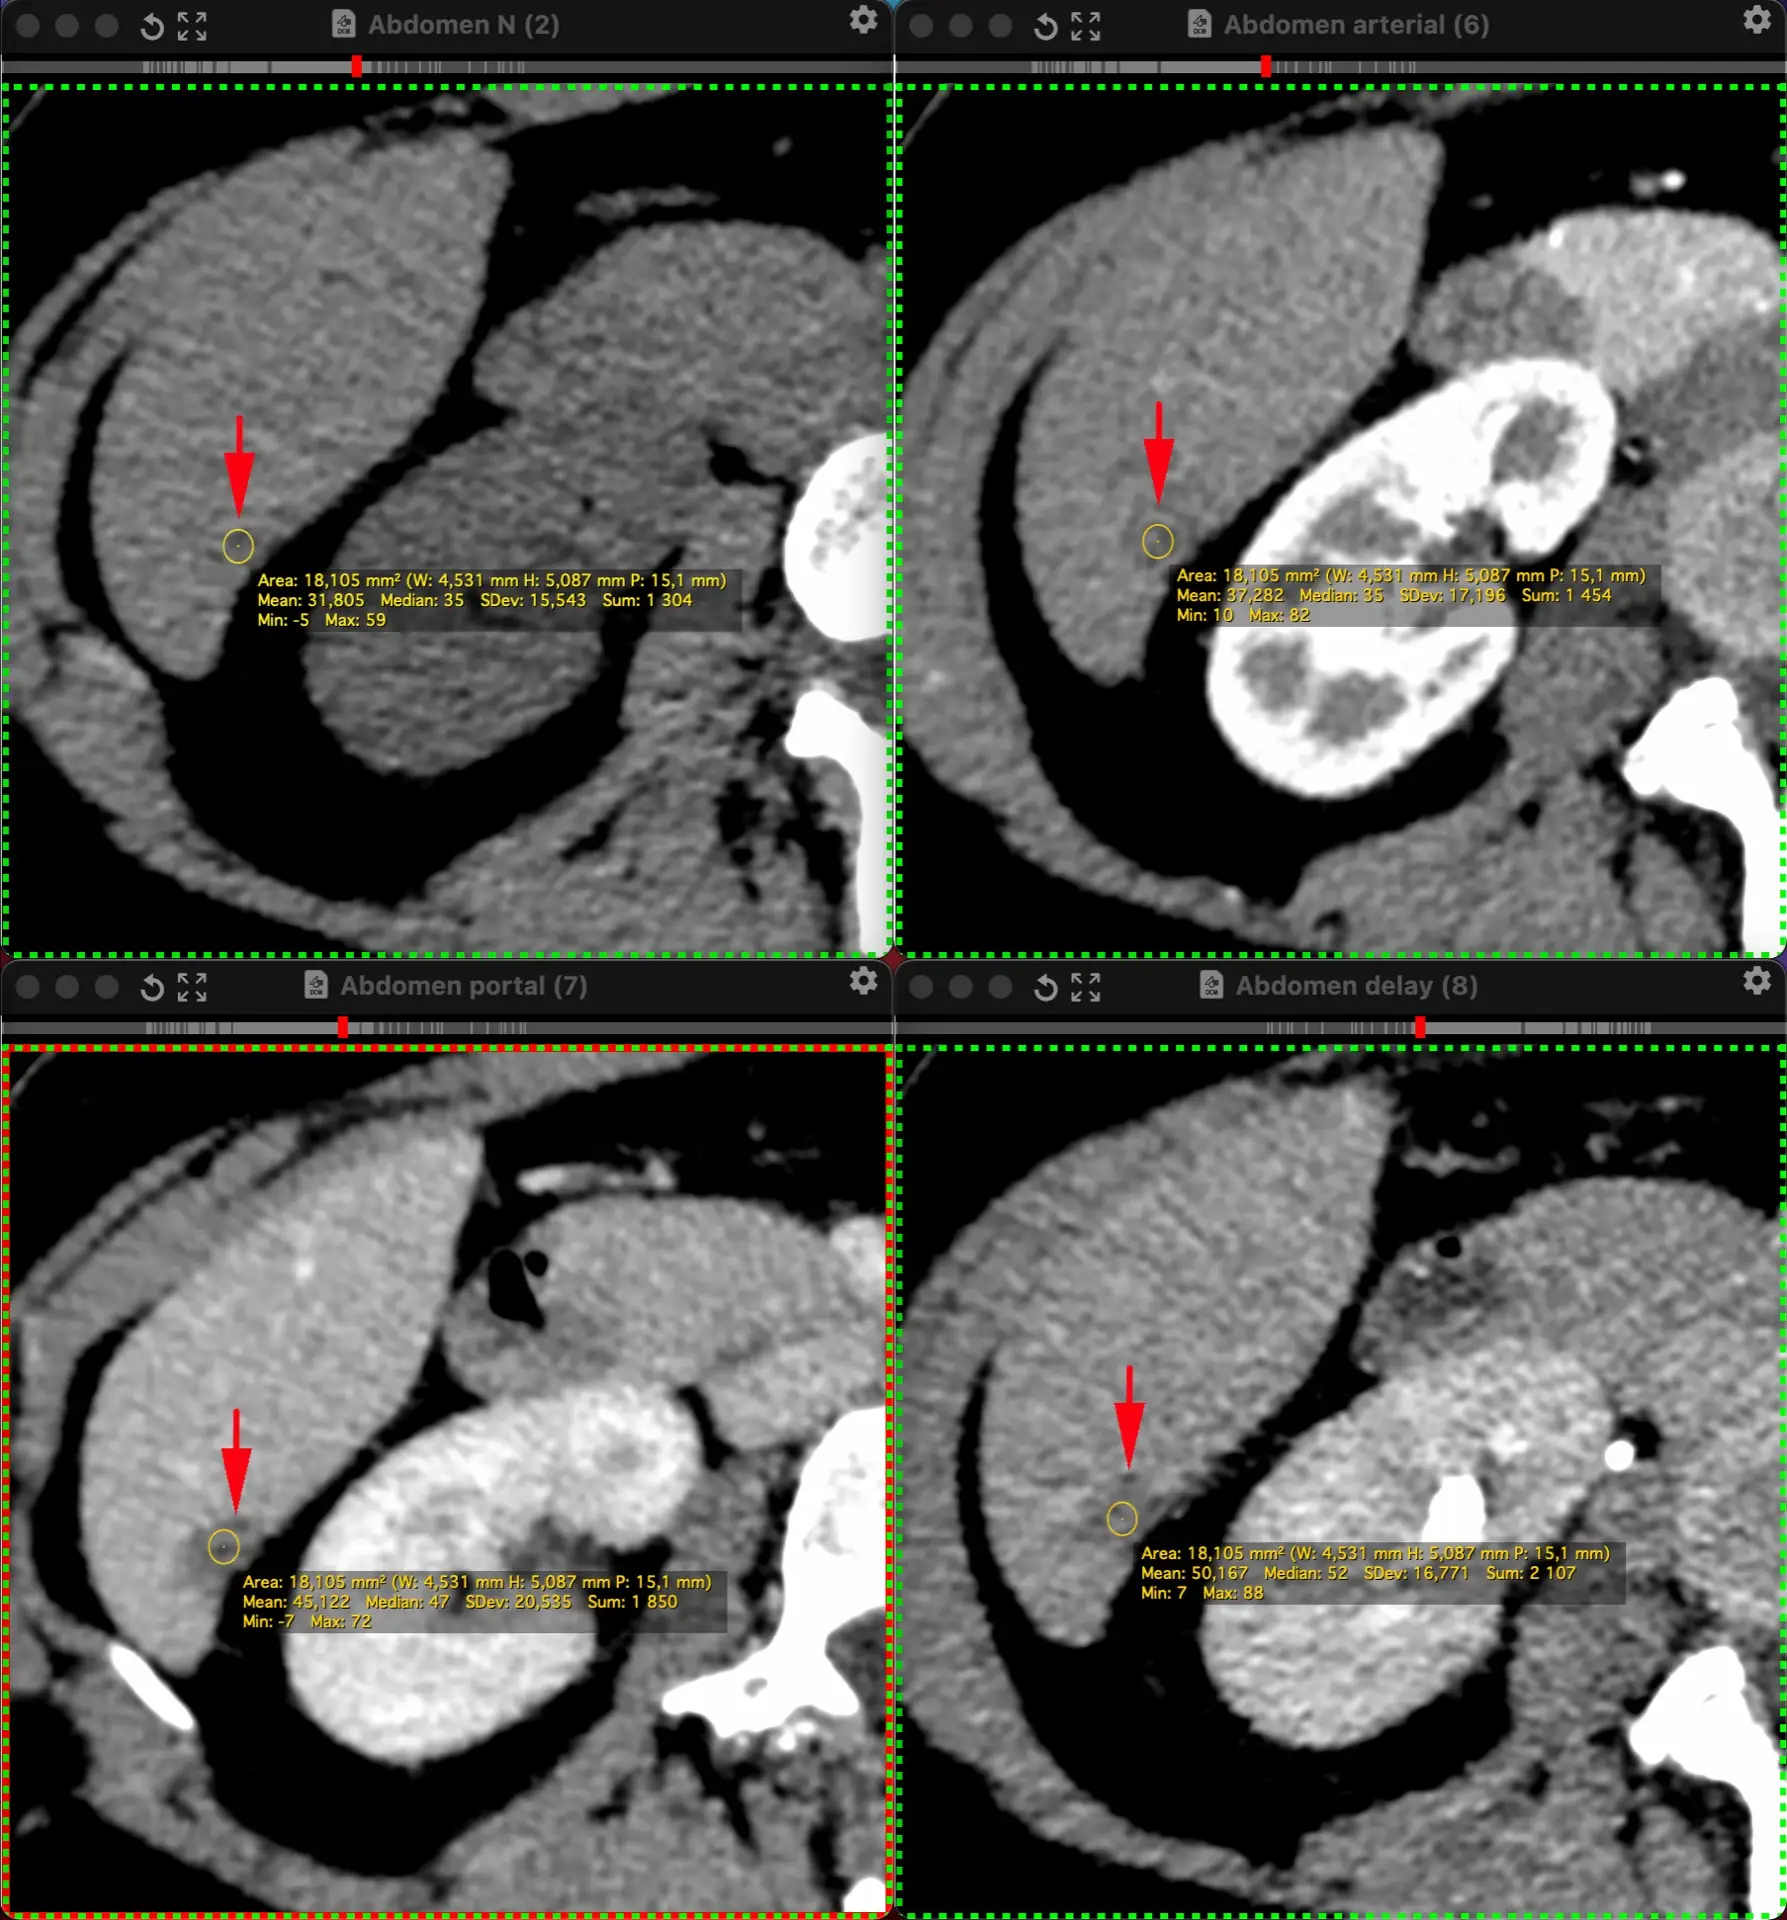

ЖЕНЩИНА 38 лет, фокальное изменение печени выявлено на УЗИ.

Повторные #КТ (с разницей в 2,5 месяца) без динамики. Имеется медленное, постепенное, слабоинтенсивное накопление контраста от периферии к центру.

На #МРТ - очень высокий сигнал на Т2, низкий на Т1, «лучистые» контуры. Истинное ограничение диффузии (ADC=460±109х10-6 кв.мм/с). Накопление контраста такое же, но на МРТ лучше видны краевое узелков накопление в артериальную фазу, тотального контрастирования нет даже на отсроченной фазе (через 5 минут).

Картина характерна: это гиалинизированная/ #склерозированнаягемангиома. Характерное стяжение контура является свидетельством склерозирования: уменьшения объёма, «рубцевания».

Гемангиомы с суженными кавернозными пространствами из-за склероза имеют большее количество более толстых и неровных перегородок, которые могут препятствовать диффузии молекул, что приводит к снижению значений ADC.

Склерозированные гемангиомы печени — это редкие доброкачественные поражения, которые часто трудно отличить от злокачественных, ибо они не имеют типичных для кавернозных гемангиом признаков.

Но! Часть признаков все равно сохраняются:

1. Значительный гиперсигнал на т2

2. Резкие, хоть и неровные, контуры

3. Центрипетальное, и иногда с приставочными узелками накопления контраста на артериальной фазе, контрастирование, пусть и неполное.

4. Стабильность в динамике